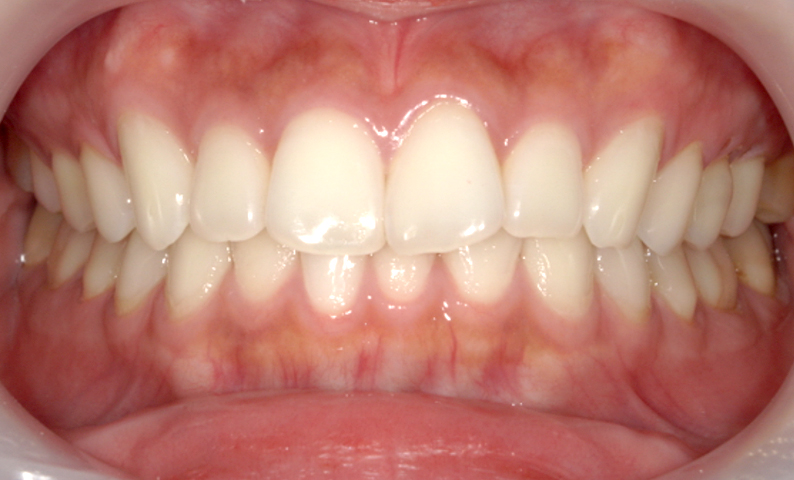

症例_002 前歯「捻転歯」症例

治療期間:7ヶ月金額:27万円+税20代女性少しのねじれ上の前歯だけ

| Before | After |